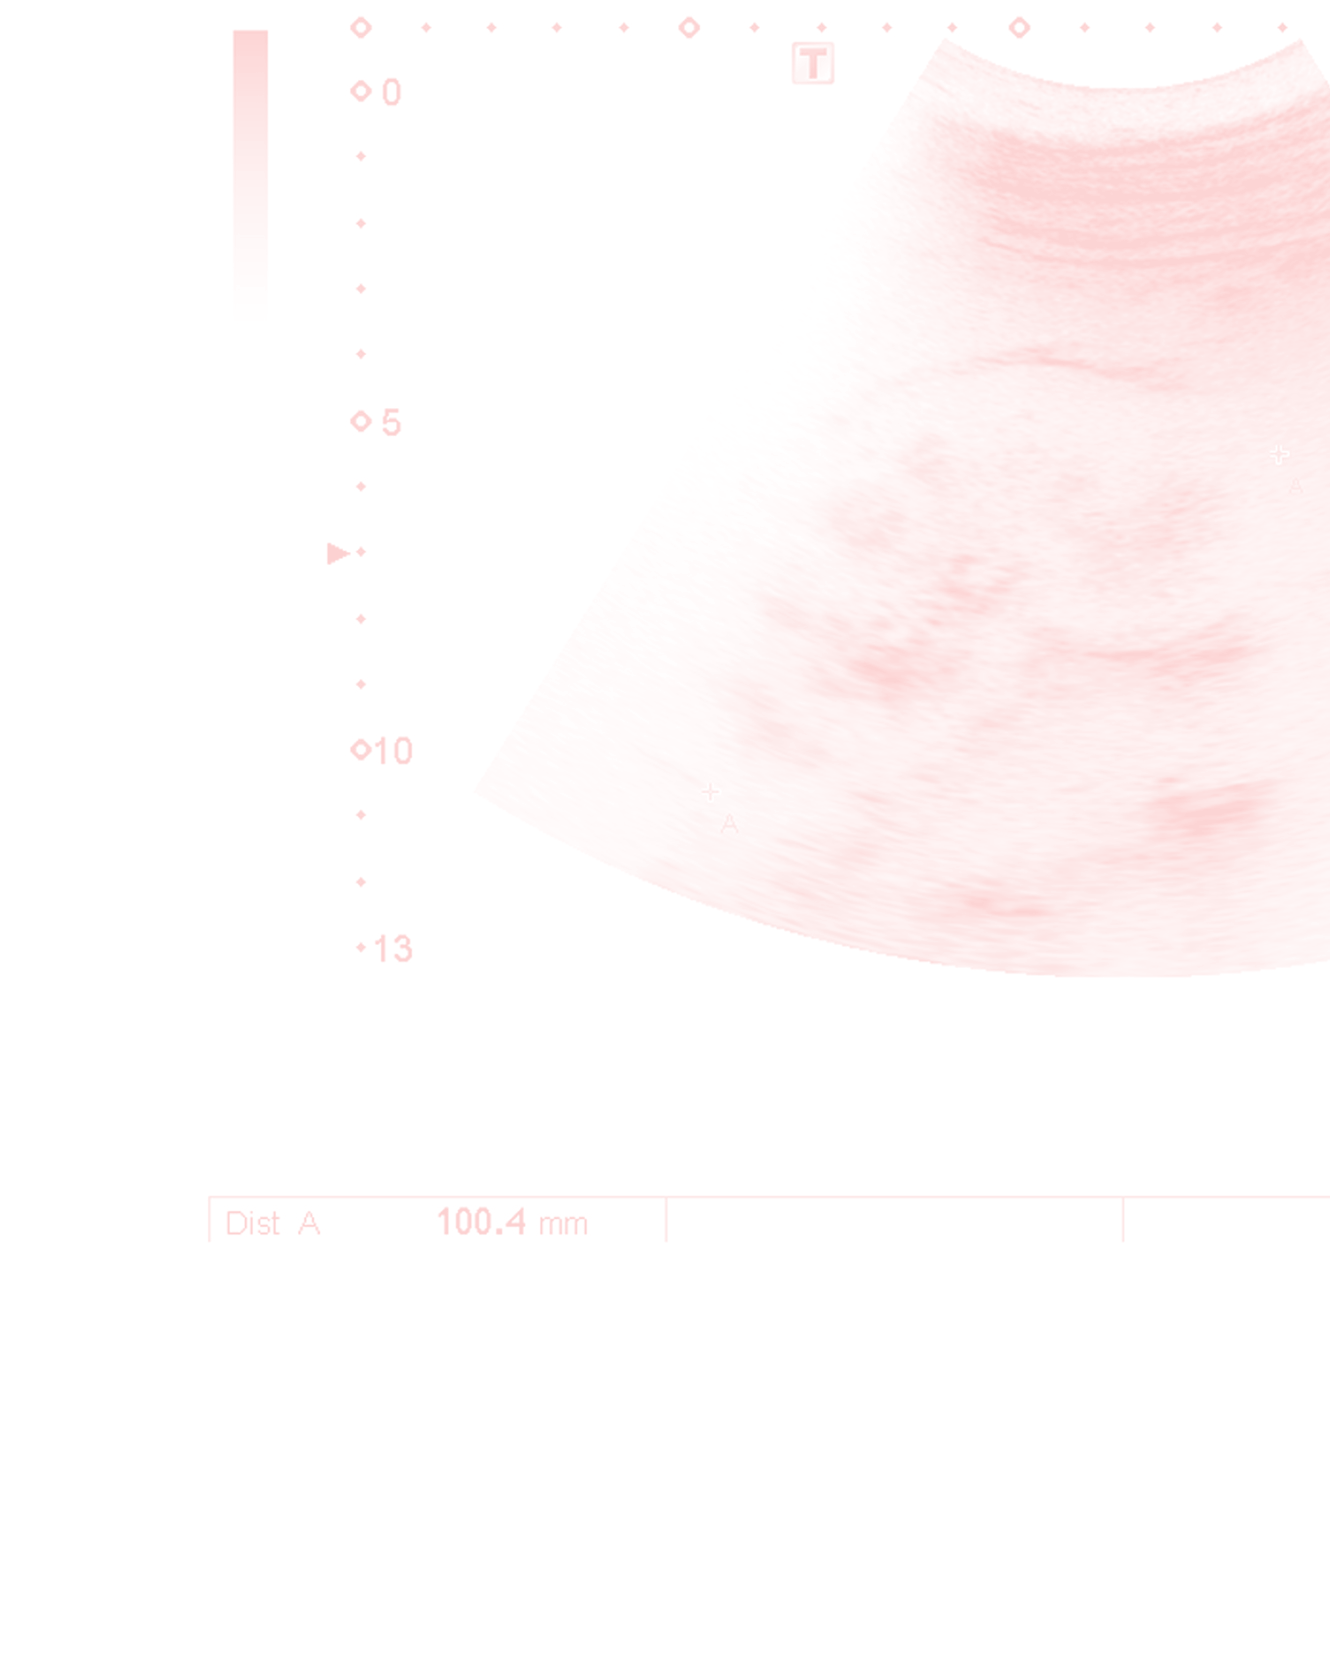

Renal & Abdominal Ultrasound

These exams are non-invasive diagnostic procedures used to evaluate blood flow in the arteries supplying your kidneys (renal arteries) and intestines (mesenteric arteries). These studies help us identify and monitor conditions that can significantly affect your health, including renal artery stenosis (narrowing of the kidney arteries) and mesenteric ischemia (reduced blood flow to the intestines).